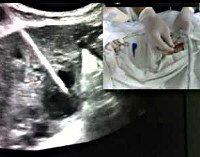

Дренирование кисты печени. Методика чрескожной катетеризации патологической полости в печени. Чрескожное дренирование кист печени проводится под контролем ультразвука или рентгеновских лучей. Через межреберье в положении больного с левой стороны производится пункция патологической полости с аспирацией содержимого. Направляющая шнура проходит через прокалывающую иглу, вдоль которой после удаления иглы вводится дренаж с боковыми перфорациями и прикрепляется к передней брюшной стенке. Через дренаж полость промывается антисептическими и антибактериальными растворами.

Также возможно лапароскопическое наложение наружной дренажной системы на патологическую кистозную полость печени. Лапароскопический метод обеспечивает доступ к полостным массам, дренирование которых чрескожным методом невозможно или сопряжено с высоким риском, предотвращает попадание содержимого кист в брюшную полость, позволяет рассекать стенки многокамерных образований и максимально эвакуировать содержимое, провести детальную ревизию брюшной полости. В процессе лапароскопического дренирования кисты печени проводится пункционная аспирация содержимого полости, ее вскрытие, санация и наружный дренаж.